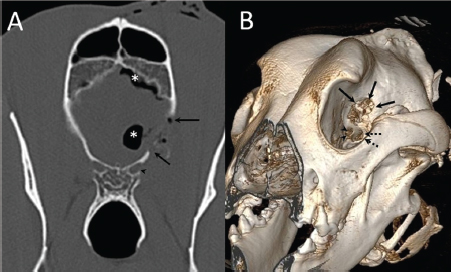

A 3-year-old female Great Dane was referred for acute onset behavioral changes (aggression and disorientation) of 2 weeks duration, and seizures from 24 hours prior to presentation. Physical examination revealed no abnormalities in body temperature, body condition score, heart rate, pulse quality, or cardiopulmonary auscultation. All lymph nodes were considered of normal size and no pain was elicited upon manipulation of the orbital, aural, or cranial musculature. Neither was there any history of dermatological or traumatic lesions in the eye, ear, or mouth. The neurological examination revealed the patient to be obtunded with decreased postural reactions and menace response worse in the left side. Neuroanatomic lesion localization was considered focal in the right prosencephalon with a possible increase in intracranial pressure. Hematological and serum biochemical analysis showed no abnormalities. Magnetic resonance imaging was performed using a low-field magnet (Airis Mate; Hitachi, Tokio, Japan). The study revealed a left-sided single frontal intra-axial lesion affecting gray and white matter adjacent to the internal capsule at the level of the optic canal (Fig. 1). The lesion presented signal homogeneity characterized by hyperintensity on T2W and FLAIR sequences and hypointensity in T1W sequences with peripheral enhancement after intravenous contrast administration (Fig. 1A and 1B). The lesion had a round shape with the greatest diameter of 2.84 cm. This enhancement was also recognized in the surrounding meninges following the brain surface following sulci. A small linear tract observed was directed dorsally from the lesion through the corona radiata (Fig. 1B). The lesion was associated with extensive perilesional vasogenic edema that worsened the mass effect characterized by a midline shift. The orbital and medial pterygoid muscles also showed an intense enhancement (Fig. 2). The wing of the presphenoid bone was thinner than the contralateral bone (Fig. 1B). A CT scan (Astelion 16, Toshiba, Tokio, Japan) was performed after MRI that allowed the identification of osteolysis in the presphenoid bone immediately dorsal to the orbital fissure (Fig. 1C). CT scan also revealed a hypoattenuating intra-axial lesion located in the left frontoparietal lobe together with diffuse hypoattenuation of tissues adjacent to the left optic nerve and the left pterygoid muscle. Finally, CSF analysis showed no abnormalities. On the basis of advanced radiological findings, the main differential diagnosis was an intracranial abscess due to the extension of the extracranial septic process through presphenoid bone. Because of rapid neurologic deterioration and suspected increased intracranial pressure, surgical excision was planned. A modified left rostrotentorial craniectomy was performed. Temporalis muscle and fascia were retracted, extending the incision cranially through the temporal line. Once the frontal and presphenoid bones were exposed an area of osteolysis was observed in the wing of the presphenoid bone immediately dorsal to the orbital fissure. The craniectomy (approximately 3 cm diameter) was centered on the osseous defect. A mucopurulent discharge presented immediately after the incision of the dura mater. A sample was collected for its microbiological study. The surgical site was flushed with sterile saline revealing the tip of a grass awn which was extracted from the brain parenchyma together with a small amount of purulent fluid (Fig. 3). After extensive flushing, the meninges were left open to allow drainage and the incision was closed as per routinely. Postoperative CT showed the correct location of the craniectomy and resolution of the abscess which was substituted by gaseous content but remained inside and on the dorsal surface of the frontal lobe (Fig. 4). Immediate postoperative therapy consisted of amoxicillin + clavulanic acid (Synulox 500, Zoetis Spain SL) 22 mg/kg PO, q8h; marbofloxacin (Marbocyl P80, Vetoquinol SA) 5 mg/kg PO, q24h; metronidazole (Flagyl 250, Sanofi-aventis SA) 15 mg/kg PO, q12h; prednisone (Prednisona Kern Pharma 30mg, Kern Pharma) 0.5 mg/kg PO, q12h; tramadol (Tramadol retard Combix 100 mg, Laboratorios Combix S.L.U) 2 mg/kg PO, q8h; famotidine (Famotidina Normon 40 mg; Laboratorios Normon SA) 0.7 mg/kg PO, q24h; and phenobarbital (Phenoleptil 100 mg, Le Vet BV) 2.5 mg/kg PO, q12h. Cultured samples were positive for Pseudomonas aeruginosa sensitive to ciprofloxacin, imipenem, and amikacin among other antibiotics. Based on these results, antibiotic therapy was changed to ciprofloxacin (Ciprofloxacino 500, Laboratorios Normon SA) 10 mg/kg PO, q12h and metronidazole 15 mg/kg PO, q12h for 2 months. Prednisone, tramadol, and famotidine were withdrawn and phenobarbital was maintained at 2.5 mg/kg q12h. Six-month post-operative revision magnetic resonance revealed no signs suggesting the existence of an inflammatory process (Fig. 5). In the area where the abscess had been located, a fluid-filled cavity suggesting being CSF was observed. One year follow-up revealed the patient had seizures every 3 months with neurological examination remaining normal. The patient died 2 years later of unrelated causes.

Fig. 2. (A) Transverse and (B) dorsal post-contrast T1-weighted images revealing enhancement of orbital musculature and medial pterygoid muscle (arrows).

Fig. 4. (A) Transverse and (B) 3D reconstruction postoperative CT images. Note increased defect on the presphenoid bone (arrows) immediately dorsal to the optic canal (arrowhead) and orbital fissure (dotted arrow). Also, note the presence of hypoattenuating content inside and over the dorsal surface of the frontal lobe (asterisks) compatible with air.